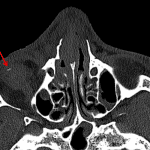

- Acute mildly displaced fracture of the right frontal process of the maxilla and nondisplaced right nasal bone fracture

- Tiny radiopaque foreign body along the anteroinferior margin of the right globe

- Trace extraconal hemorrhage in the superomedial right orbit

- Extensive facial swelling/contusion, greatest in the right periorbital region

- Moderate mucosal thickening of the paranasal sinuses

- Acute nasal fractures

- Orbital foreign body

Acute mildly displaced fracture of the right frontal process of the maxilla and nondisplaced right nasal bone fracture.

3 mm radiopaque foreign body along the anteroinferior margin of the right globe. Trace extraconal hemorrhage in the superomedial right orbit. No evidence of orbital wall fracture or proptosis. Globes are intact.

Extensive facial swelling/contusion, greatest in the right periorbital region.

Moderate mucosal thickening of the paranasal sinuses.